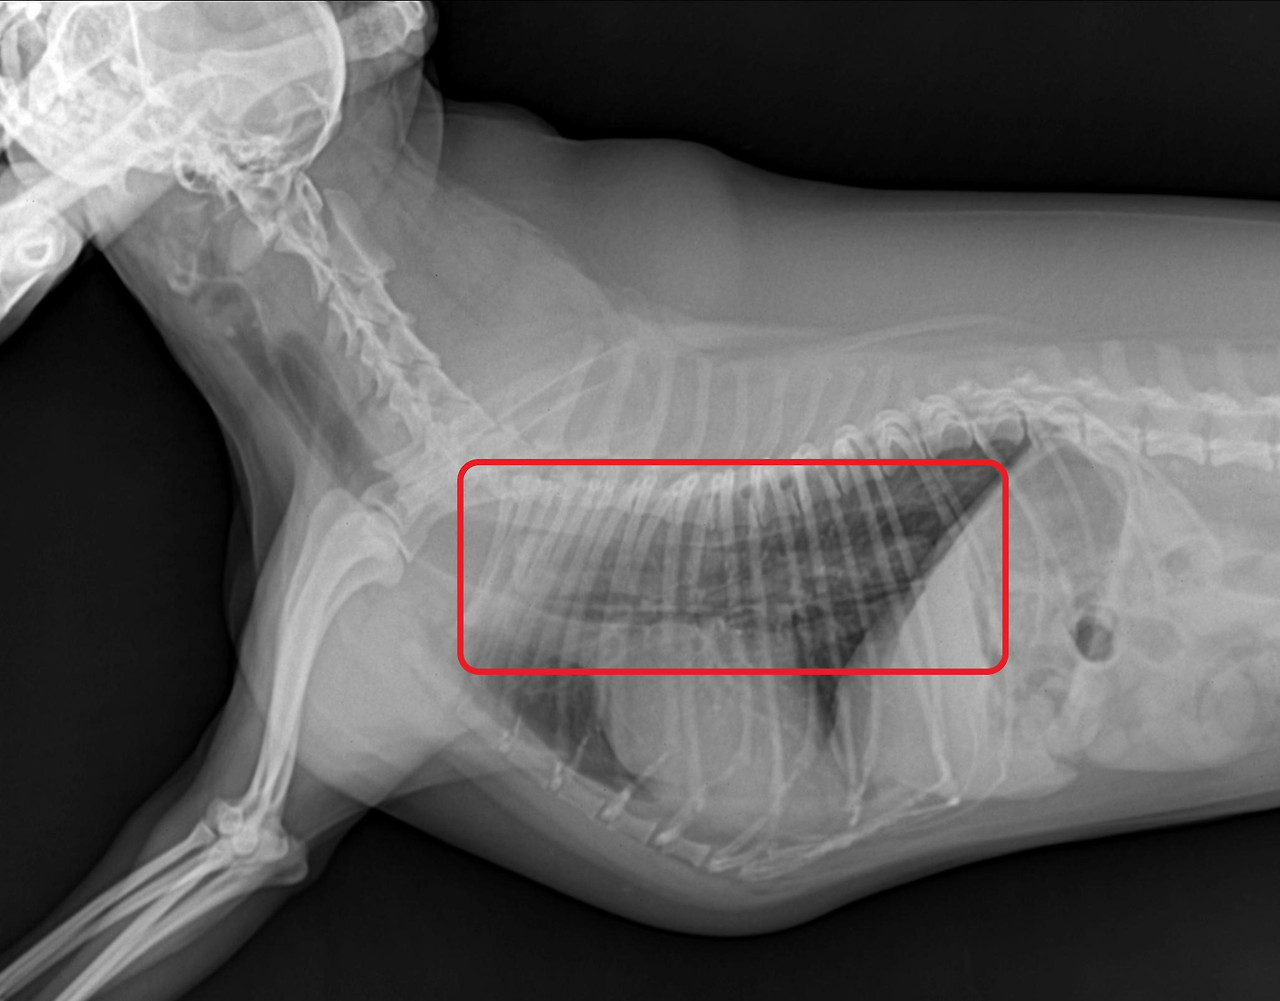

강아지가 이물을 먹어서 병원에 오는 사례

2.jpg

1.jpg

<좌> 식도에 사과가 걸린 경우 내시경 사진, <우> 식도에 개껌이 걸린 경우 방사선 사진

사진출처 : 24시 센트럴 동물 메디컬센터

아동기는 호기심이 왕성하고 에너지가 넘치는 시기라고 말씀드렸는데요,

이 때문에 먹어서는 안 되는 이물을 먹거나 급하게 먹다가 식도에 걸려서 병원에 오는 사례가 많습니다.

3.jpg

KakaoTalk_20200529_124245332.jpg

<좌> 식도에 간식이 걸린 경우 <우> 위에 옷핀과 동전이 있는 경우